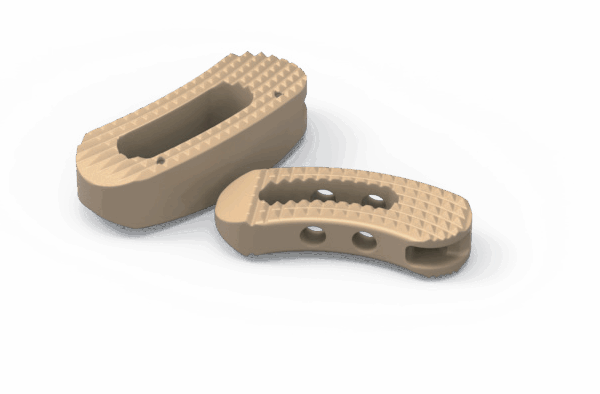

Sistema de cages para fusão intersomática, com diferentes modelos (Coales-P, C, M, T, L e Mesh), em PEEK, com marcadores de tântalo para melhor visualização e adesão óssea.

- Medidas: Diversas opções de altura, largura e ângulo de lordose.

- Usos principais: Fusão espinhal lombar e cervical, oferecendo estabilidade e suporte biomecânico.

- Tipo de produto: Cages intersomáticos para coluna vertebral.

- Compatibilidade: Compatível com técnicas de fusão TLIF, PLIF, ACIF, etc.

Design anatômico • Radiotransparente • Marcadores de tântalo para visualização • Reduz risco de subsistência